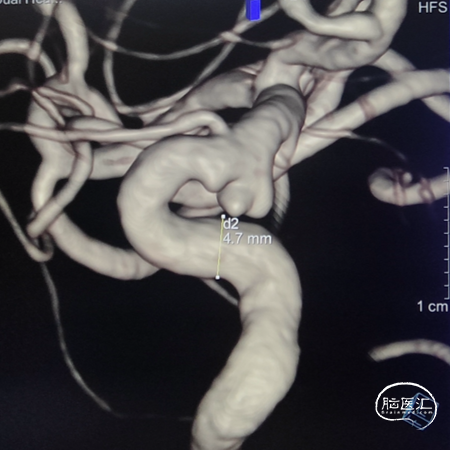

左侧颈内动脉造影:左侧颈内动脉C6段动脉瘤。

左侧颈内动脉三维重建:左侧颈内动脉C6动脉瘤。

术前3D造影